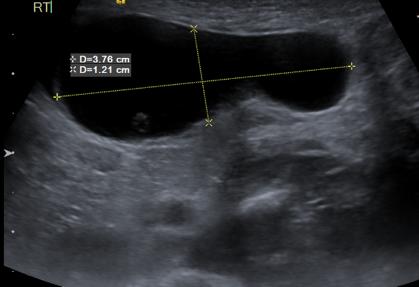

Intrauterine testicular torsion: A case report

Introduction: Intrauterine testicular torsion is a relatively rare but serious entity of the neonatal period. It is often diagnosed at birth or within the first hours of life, while prenatal detection remains challenging. Timely diagnosis and management undoubtedly pose a significant challenge for the pediatrician.

Method: We describe a case of a full-term male neonate, with normal prenatal ultrasound findings, born with a prominent swelling in the right inguinal region without signs of local inflammation. Further investigation was performed with a scrotal and inguinal ultrasound.

Results: The ultrasound findings were more consistent with a right spermatic cord cyst, with a suspicion of micro-rupture. This finding was considered extremely rare by pediatric surgeons for a newborn. Since intrauterine testicular torsion could not be ruled out despite the inconsistent ultrasound, the young patient was immediately therefore referred to a pediatric surgical clinic, where testicular torsion was diagnosed. As the testis maintained some degree of perfusion, bilateral orchiopexy was performed.

Discussion: Intrauterine testicular torsion is usually diagnosed after birth, when the damage to the testis is already irreversible. The painless clinical presentation may lead to a delayed diagnosis, while Doppler ultrasound, although useful, should not delay surgical exploration in suspicious cases. Despite the low probability of salvaging the affected testis, surgical intervention is essential to confirm the diagnosis and prevent contralateral torsion through prophylactic orchiopexy. Early recognition by the pediatrician and prompt collaboration with the pediatric surgeon are crucial for the optimal management of this rare neonatal condition.